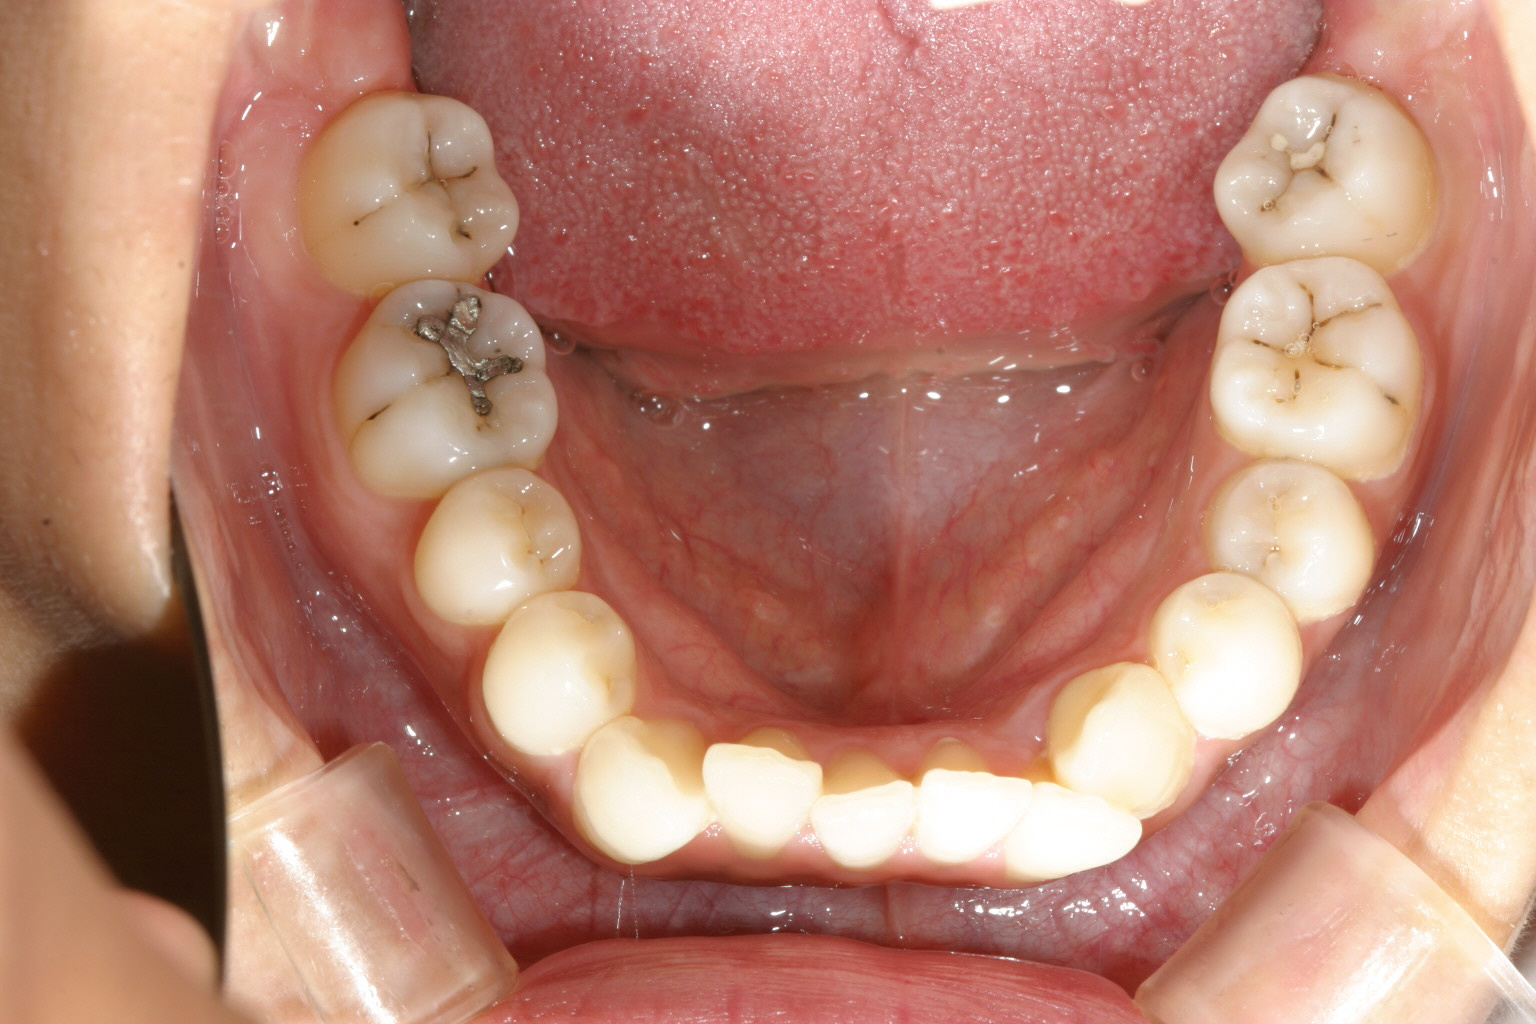

下顎は上顎程では無いですが少し叢生になっています。

下顎も綺麗ですね~